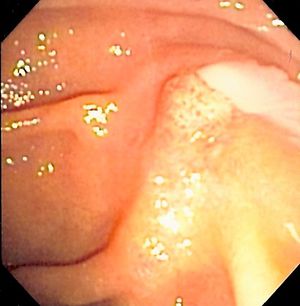

صورة منظار للاثني عشر لبثق صديد من أمبولة ڤاتر، مما يدل على التهاب الأقنية الصفراوية. | |

The gold standard test for biliary obstruction is still endoscopic retrograde cholangiopancreatography (ERCP). This involves the use of endoscopy (passing a tube through the mouth into the esophagus, stomach and thence to the duodenum) to pass a small cannula into the bile duct. At that point, radiocontrast is injected to opacify the duct, and X-rays are taken to get a visual impression of the biliary system. On the endoscopic image of the ampulla, one can sometimes see a protuberant ampulla from an impacted gallstone in the common bile duct or the frank extrusion of pus from the common bile duct orifice. On the X-ray images (known as cholangiograms), gallstones are visible as non-opacified areas in the contour of the duct. For diagnostic purposes, ERCP has now generally been replaced by MRCP. ERCP is only used first-line in critically ill patients in whom delay for diagnostic tests is not acceptable; however, if the index of suspicion for cholangitis is high, an ERCP is typically done to achieve drainage of the obstructed common bile duct.[1]